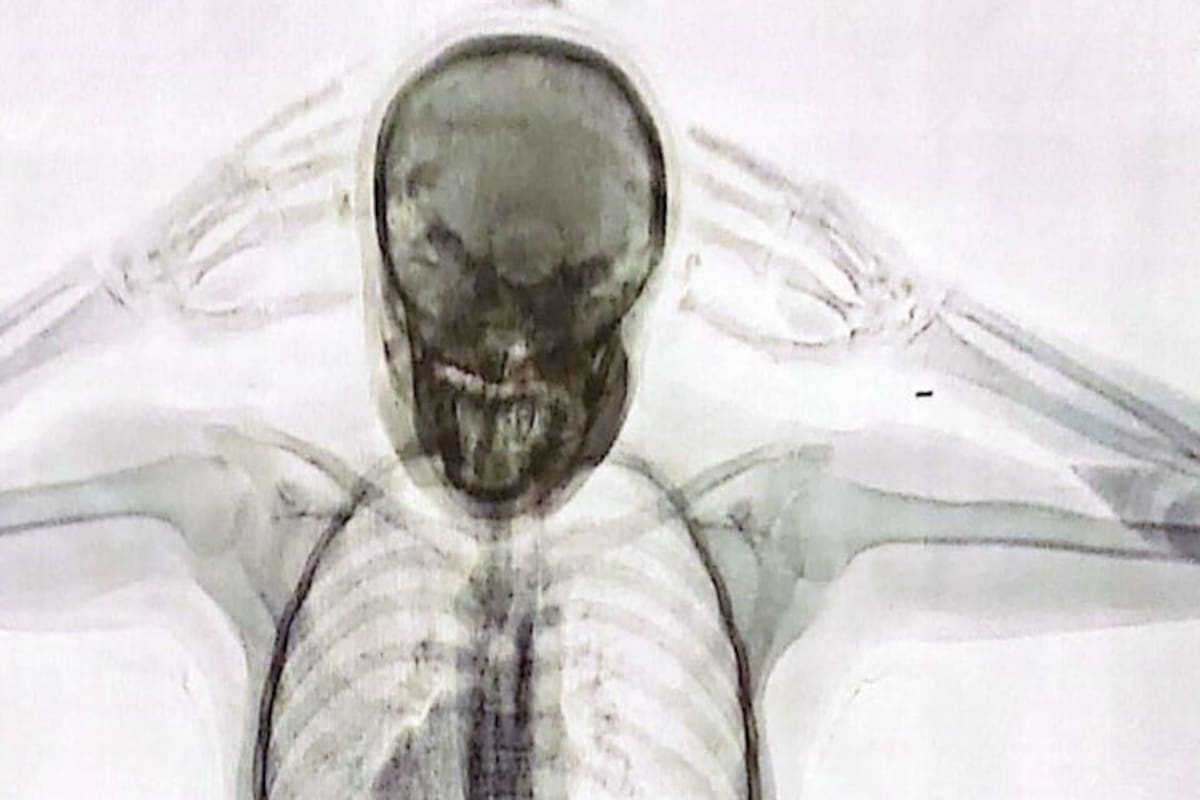

La noticia de la detención de A.S.F. fue publicada por LA NACION hace 11 días, cuando se hicieron públicas las imágenes captadas por el equipo de rayos X Body Scan que mostraban cómo se veían las 78 cápsulas con cocaína en el cuerpo de la joven pasajera.

“No solo respondió de forma dubitativa, también lo hizo de manera incongruente. Entonces, se decidió convocar a dos testigos y se le realizó un control corporal, no invasivo, mediante un equipo de rayos X denominado Body Scan. El operador del equipo técnico visualizó una imagen dudosa en cuanto a la posible presencia de cuerpos extraños en el organismo”, explicó a LA NACION una fuente de la investigación.